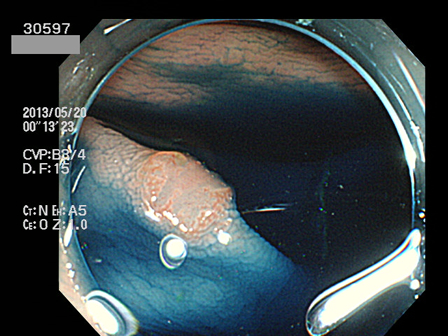

上記100名より抽出した平坦・陥凹型腺腫(=癌化の危険が高いが見落としやすい病変)の内視鏡写真

30500 30502 30504 30506 30510 30512 30513 30519 30520 30521 30523 30524 30526 30529 30530 30532 30533 30534 30535 30540 30543 30545 30546 30548 30551 30552 30554 30555 30558 30560 30561 30562 30564 30565 30568 30571 30572 30573 30574 30575 30576 30583 30584 30585 30586 30587 30588 30591 30592 30593 30596 30597・・・・・・の52名